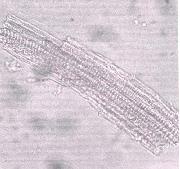

c) Thickened vessels

- (c) Adjacent spirally and annularly thickened vessels of the leaf midrib with accompanying short fibers ( Magnifications: All x 250).